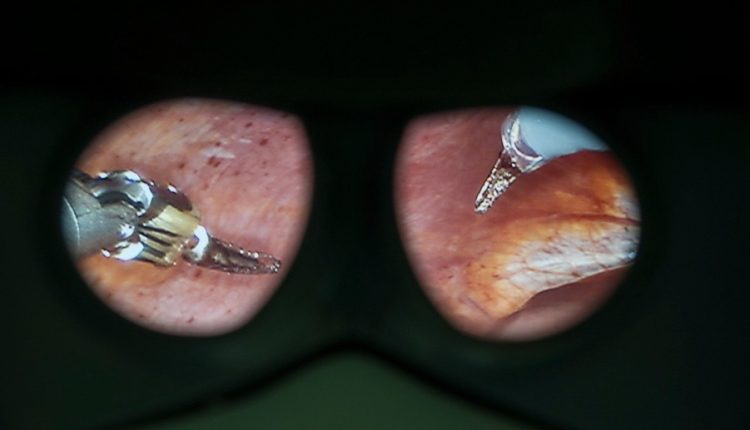

Nell’ambito quindi dell’applicazione “tailored” dello “step-up approach”, ecco le procedure dell’approccio multidisciplinare della casistica pisana: posizionamento di drenaggi percutanei ECO o TC guidati, effettuati da clinici e radiologi interventisti, drenaggio endoscopico mediante eco-endoscopia operativa, derivazioni interne chirurgiche delle raccolte e della necrosi pancreatica con tecniche mini invasive laparoscopiche/robot-assistite o tradizionali, fino alla necrosectomia con mini-laparotomie eco-guidata o classica, espressione quest’ultima della massima aggressività chirurgica.

“Aspetto particolarmente innovativo della nostra esperienza – dichiarano gli autori – è l’introduzione della tecnologia robotica anche per il trattamento di alcune forme di pancreatite acuta grave. Nell’ambito dell’approccio personalizzato, infatti, si è aggiunta recentemente la possibilità per questi pazienti di essere operati con il da Vinci Xi, nel contesto del Centro multidisciplinare di Chirurgia robotica dell’Aoup e questo consente di eseguire manovre estremamente delicate, alcune sotto guida ecografica, come asportare la necrosi pancreatica, aspirare raccolte e scegliere il punto ottimale di sutura tra le voluminose raccolte esito della pancreatite acuta e il tratto gastrointestinale. Farsi carico di questi pazienti così delicati è sempre un impegno gravoso – concludono gli autori – ma l’esperienza di tanti anni ci permette oggi di offrire loro le migliori prospettive possibili per uscire da situazioni potenzialmente letali e tornare a una sorprendente ottima qualità di vita.”